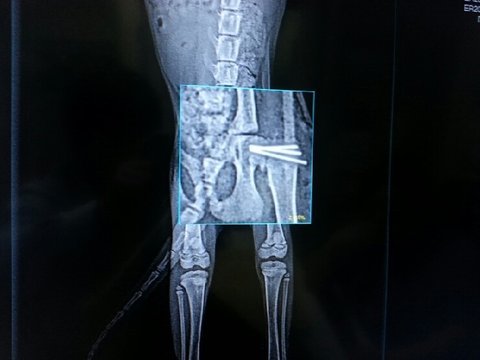

떨어져서 다쳤는데 골반이 골절상....

그래서 핀을 박는 수술도 했었구요. 레오도 고생 임보하는 사람도 고생....   특히나 많은 시간과 노력이 들어간 아이 인것 같네요^^

처음에는 부러진 부분을 깍아내고 제거한다고 했는데 제가 부탁드려서 핀을 밖고 골절된 부분을   살려내는 방향으로 해달라고 했었거든요.   근데, 의외로 고양이들이 많이 골절되는 부분이라고 하네요^^....

-> 레오 고관절 골절 상 x-ray 사진 입니다.